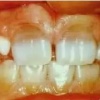

Diasteem

Diasteem – vahe esimeste hammaste vahel. Esineb 50%-l 6-8 aastastel lastel. Kuni 2 mm diasteemi puhul on, peale lateraalse intsisiivi ja silmahamba lõikumist, võimalik diasteemi iseeneslik sulgumine. Diasteem, mille suurus...